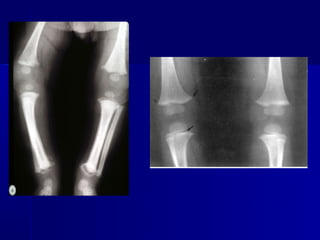

   Lesões ósseas - periostite, osteocondrite

(Wegner) e osteomielite. Lesões poliostóticas

e simétricas.

   Ossos afetados: fêmur, tíbia, úmero e fíbula.

   Pseudo paralisia de Parrot.

Sífilis Congênita Tardia

Quadro Clínico

•   Lesões a partir do segundo ano de vida.

•   Lesões cutâneas: sifílides nodulares e gomas.

•   Tíbia em lâmina de sabre e Juntas de Clutton.

   Raio X de ossos longos.

Sífilis Congênita Tardia Quadro Clínico • Lesões a partir do segundo ano de vida. • Lesões cutâneas: sifílides nodulares e gomas. • Tríade de Hutchinson - queratite intersticial, surdez do oitavo par (neurolabirintite) e dentes de Hutchinson. • Queratite intersticial:fotofobia, dor e atrofia óptica. • Neurolabirintite: bilateral, surdez total. • Dentes de Hutchinson: incisivos centrais superiores. • Perfuração do septo nasal e palato. • Tíbia em lâmina de sabre e Juntas de Clutton.

Sífilis Congênita Diagnóstico  Pesquisa direta de Treponema pallidum : Lesões de pele, mucosas, placenta e coto umbilical.  Testes sorológicos: VDRL, RPR, FTA-Abs, ELISA,TPHA, FTA Abs com a fração 19S- IgM.  Análise do T.pallidum com antígenos recombinantes.  LCR.  Anátomopatológico.  Raio X de ossos longos.  Hemograma completo,provas funcionais hepática e renal.